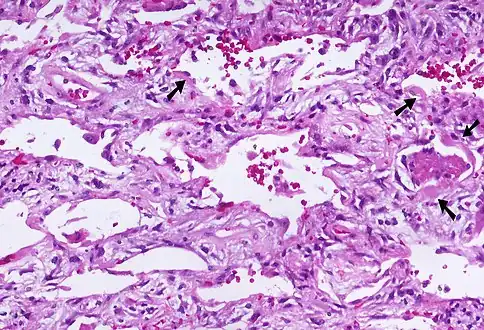

Micrograph of diffuse alveolar damage, the histologic correlate of acute interstitial pneumonitis. H&E stain.

Rapid progression from initial symptoms to respiratory failure is a key feature. An X-ray that shows ARDS is necessary for diagnosis (fluid in the small air sacs (alveoli) in both lungs). In addition, a biopsy of the lung that shows organizing diffuse alveolar damage is required for diagnosis. This type of alveolar damage can be attributed to nonconcentrated and nonlocalized alveoli damage, marked alveolar septal edema with inflammatory cell infiltration, fibroblast proliferation, occasional hyaline membranes, and thickening of the alveolar walls. The septa are lined with atypical, hyperplastic type II pneumocytes, thus leading to the collapse of airspaces. Other diagnostic tests are useful in excluding other similar conditions, but history, X-ray, and biopsy are essential. These other tests may include basic blood work, blood cultures, and bronchoalveolar lavage. The clinical picture is similar to ARDS, but AIP differs from ARDS in that the cause for AIP is not known.